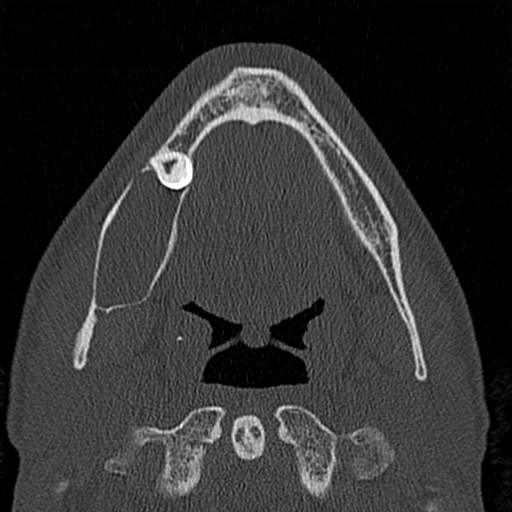

Ein ergänzend durchgeführtes Denta-CT des Unterkiefers (Abbildungen 2 und 3) zeigte eine zystische Raumforderung im Bereich der rechten Unterkieferhälfte, welche bis weit in den aufsteigenden rechten Unterkieferast reichte. Der Nervkanal des rechten N. mandibularis verlief durch die Raumforderung und ließ sich nicht sicher abgrenzen.